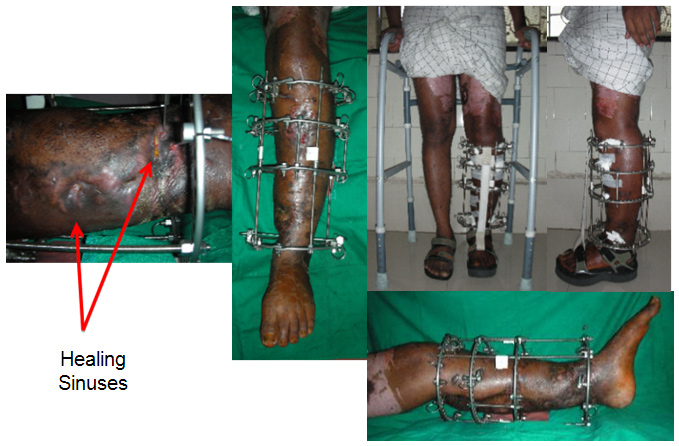

She continued to be troubled by discharge from the radial incision and another 3 weeks later the ulnar incision began discharging seropurulent fluid.

She seemed to have a 'wrist drop' which I thought was more because of adhesions or the inflamation within the compartment, rather than a problem with the radial or posterior interosseous nerve.

The only option really in my opinion was to do a proper debridement, clear the infection and then think of the reconstructive aspect.